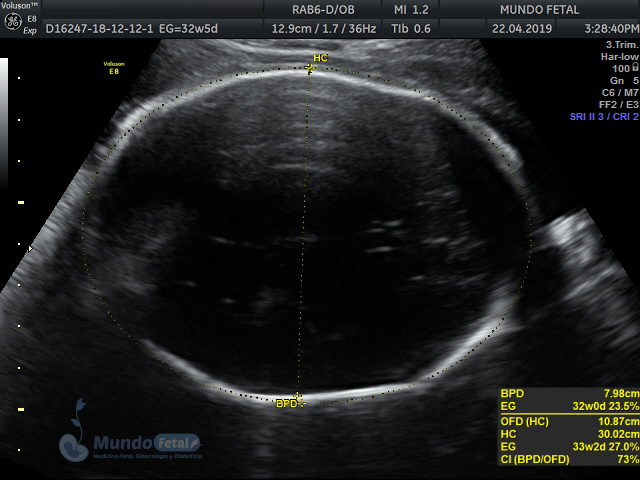

Mediante esta técnica ultrasonográfica, evaluamos en tiempo real al bebe y monitoreamos electrónicamente la frecuencia cardiaca fetal, vigilando los siguientes parámetros:

A cada parámetro se le asigna un puntaje basado en una escala del 0 al 10. Se ha propuesto que en estados fetales alterados por disminución del oxígeno se alteran los parámetros de manera que podemos predecir el estado fetal evaluando estos puntos.